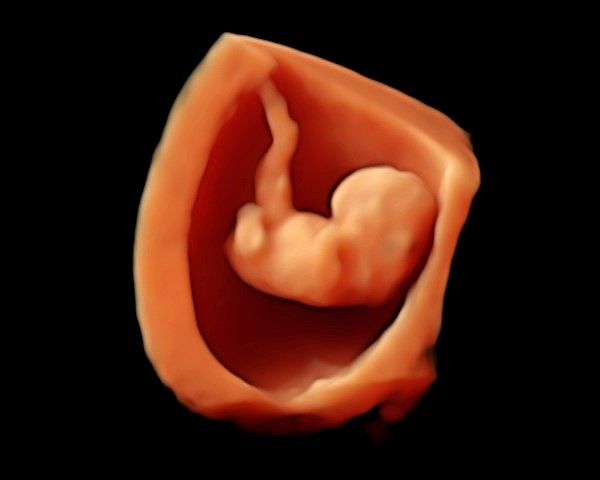

The Early Pregnancy or Viability Scan is performed in the first trimester, most commonly between 7 and 10 weeks of pregnancy. The scan is carried out to confirm that the pregnancy is developing within the womb (intrauterine), to assess viability by demonstrating a normal fetal heart rhythm where appropriate, and to ensure that the supporting structures of the pregnancy appear healthy. It also confirms the number of babies and assesses early development in relation to gestational age.

Early pregnancy scan